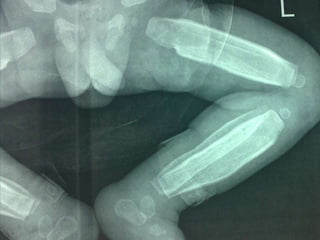

Caffey disease(ICH)AD  .subperiosteal bone formationbefore 6 months, M:f  1:1General hyperirritability, fever and anorexia, painful, firm soft-tissue swelling.PGETTT infants with cyanotic heart disease cortical hyperostosis that mimics ICH. PGE serum levels elevated Indomethacin.

Caffey disease(ICH)AD  .subperiostealbone formationbefore 6 months, M:f 1:1General hyperirritability, fever and anorexia, painful, firm soft-tissue swelling.PGETTT infants with cyanotic heart disease cortical hyperostosis that mimics ICH. PGE serum levels elevated Indomethacin.

DD  - Physiological in infant not more than 4 m.   - trauma.   - Hypervitaminosis A.   - scurvy   - prostaglandin E1 and E2 administration , 42% of infants for more than 30 days; this increases to 100% in more than 60 days.8   - infection (including syphilis)   - metastatic neuroblastoma.

DD -Physiological in infant not more than 4 m. - trauma. - Hypervitaminosis A. - scurvy - prostaglandin E1 and E2 administration , 42% of infants for more than 30 days; this increases to 100% in more than 60 days.8 - infection (including syphilis) - metastatic neuroblastoma.